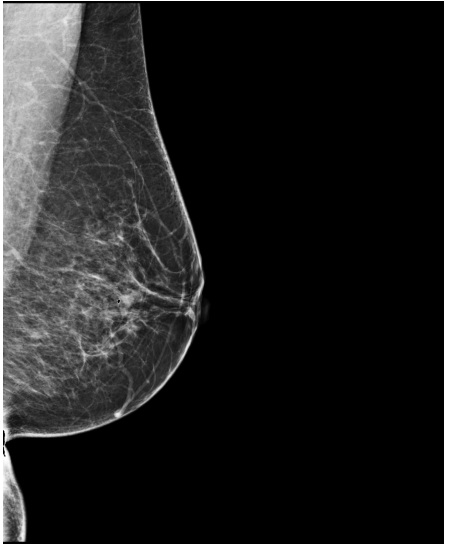

Refer to caption

(a) FeatAlign

(b) FeatAlignReg

(c) ImgFeatAlign/ImgAlign

(d) FeatAlign

(e) FeatAlignReg